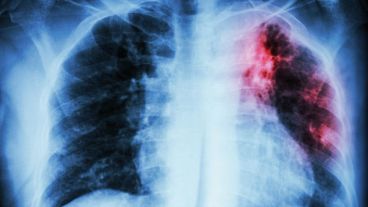

En el marco del Día Mundial de Lucha contra la Tuberculosis que se celebra el próximo 24 de marzo, el organismo señaló que el gasto mundial dedicado a la lucha contra la tuberculosis es totalmente insuficiente para relanzar la batalla contra la enfermedad tras años de lucha suspendida por la Covid-19.

En tanto, el organismo reveló con preocupación que las muertes vinculadas a la tuberculosis comenzaron a aumentar nuevamente “por primera vez en más de una década” y remarcó que la pandemia del coronavirus detuvo “años de progreso mundial en la lucha contra esta enfermedad”.